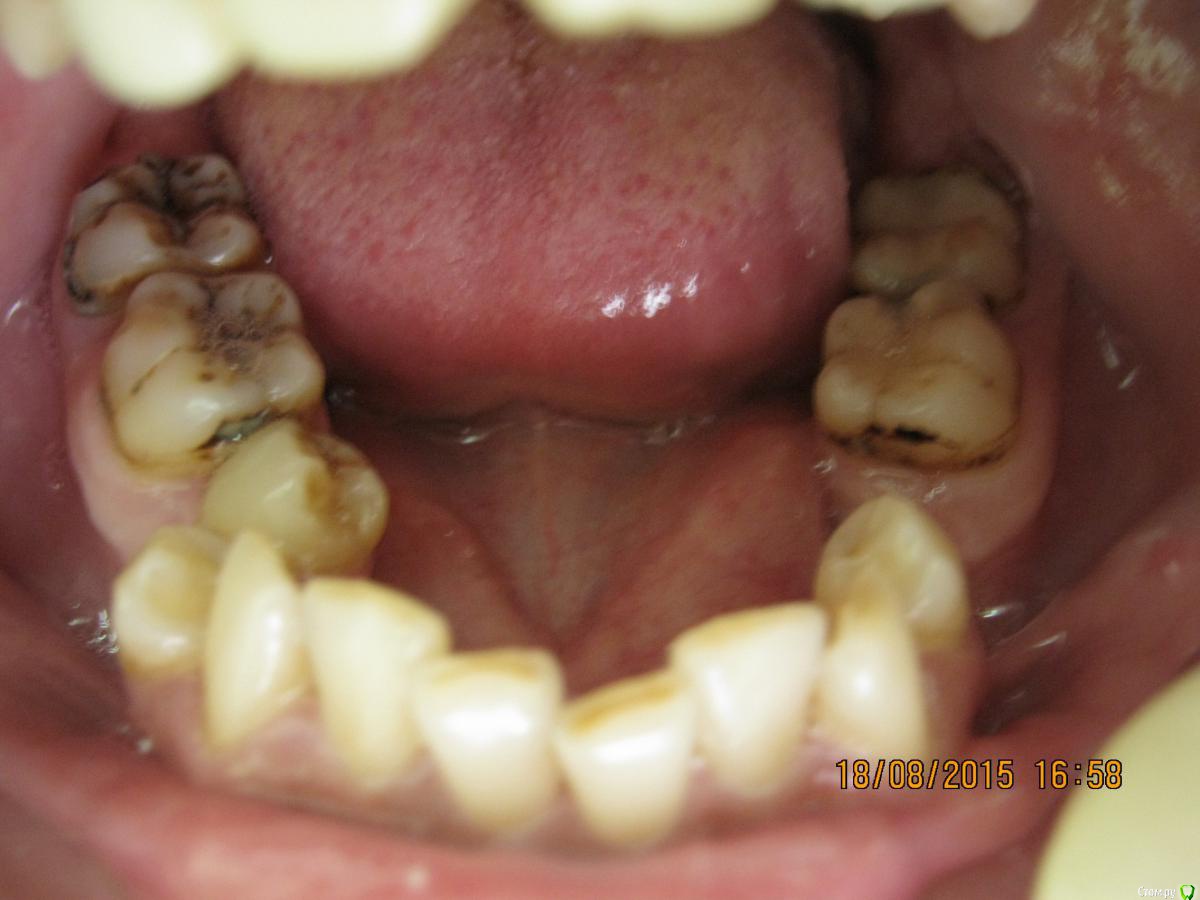

SeregaStomatolog Опубликовано 18 августа, 2015 Поделиться Опубликовано 18 августа, 2015 Добрый вечер уважаемые коллеги!В клинику обратилась пациентка с такой ситуацией во рту.Подскажите пожалуйста что можно сделать и с чего начать. Ссылка на комментарий

krokomot Опубликовано 18 августа, 2015 Поделиться Опубликовано 18 августа, 2015 Бюджет не очень большой,в пределах 50-70 т.р для такого рода патологии как-то уж совсем мало, тут еле в съемники с пару коронками влезешь. Налицо вторичные деформации, десневая улыбка у пациентки и проблемы с периодонтом*, весь букет)) А что хочет пациентка?, уж не голивуд ли?)) Ссылка на комментарий

krokomot Опубликовано 18 августа, 2015 Поделиться Опубликовано 18 августа, 2015 Сделав как хочет пациентка вы не получите красивый результат, которого она ждет! и получится что вы не смогли реализовать ее мечты , а значит доктор неахти)) да и вы не особо результатом будете довольны, вам это надо? Если в эстетике проблем нет, восстановите функцию. Ненужное удалить, длинные зубы дэпульпировать, укоротить ну и коронуйте)) Ссылка на комментарий

SeregaStomatolog Опубликовано 18 августа, 2015 Автор Поделиться Опубликовано 18 августа, 2015 Сделав как хочет пациентка вы не получите красивый результат, которого она ждет! и получится что вы не смогли реализовать ее мечты , а значит доктор неахти)) да и вы не особо результатом будете довольны, вам это надо? Если в эстетике проблем нет, восстановите функцию. Ненужное удалить, длинные зубы дэпульпировать, укоротить ну и коронуйте))Мне кажется если я возьмусь,то все равно не буду результатом доволен,т.к. все реализовать не получится.Самая большая проблема в области отсутствующих 1.6,1.7-зубо-альвеолярное удлинение 4.6,4.7 настолько велико,что они практически касаются слизистой в области 1.6,1.7. Ссылка на комментарий